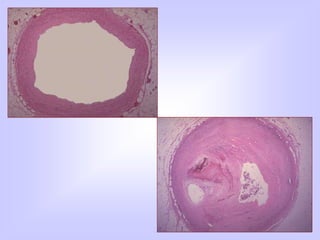

FATTY STREAK

ATHEROMATOUS PLAQUE

๏ƒ˜ FIBROUS

๏ƒ˜ FIBROFATTY

๏ƒ˜ LIPID

๏ƒ˜ FIBROLIPID PLAQUES

COMPLICATED PLAQUE

FATTY STREAK ATHEROMATOUS PLAQUE ๏ƒ˜FIBROUS ๏ƒ˜ FIBROFATTY ๏ƒ˜ LIPID ๏ƒ˜ FIBROLIPID PLAQUES COMPLICATED PLAQUE